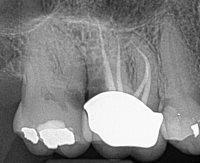

When I see a lateral radiolucency on the furcation side of a mesial root of #19 or #30 (Fig 1: around the junction of the middle and apical 1/3), I highly suspect a middle mesial (MM) canal that exits laterally.